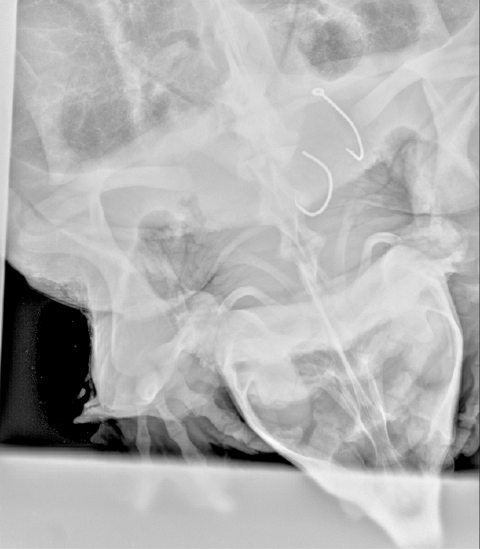

This year, scientists brought some special equipment with them: metal detectors and a portable X-ray machine. It worked.

“We were getting hits for hooks in throats,” said Pearson.

This information is important because the primary threat to the species comes from bycatch on fishing equipment. Pearson said people know that these turtles drown on trot and limb lines, but less is known about what happens with hook swallowing.

Looking inside the alligator snapping turtle will tell scientists more about the fishing hook threat. They will learn how many turtles are being affected, and what types of hooks they are swallowing the most.

“Maybe the hooks that we are seeing inside the turtles are all J hooks and not circle hooks,” said Pearson. “Maybe they are all circle hooks and not J hooks.”